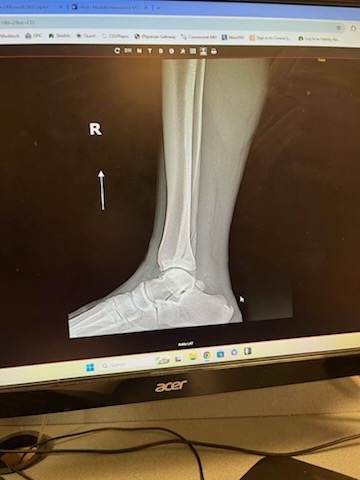

As many of you know, two weeks ago I broke my fibula while trying to catch a ball during a softball game. Unfortunately, the momentum from the play caused me to land awkwardly, and the impact snapped my leg.